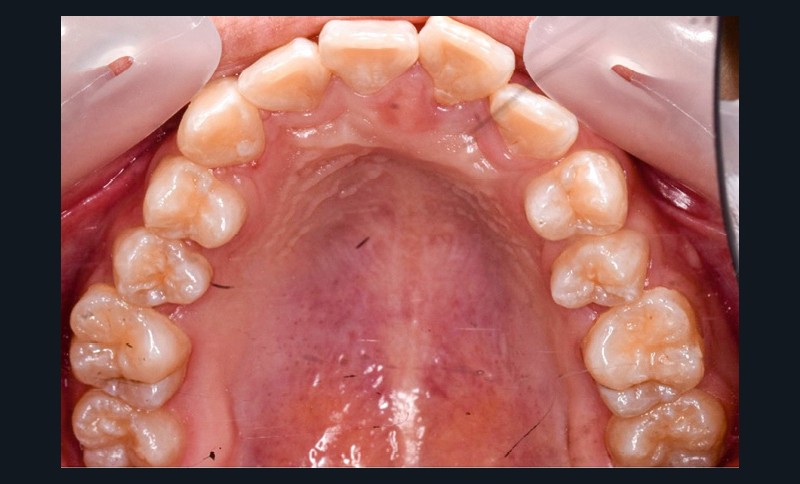

Une patiente âgée de 12 ans se présente en consultation, motivée par la position de son incisive centrale maxillaire, décrite comme « en avant », marquée par une dyschromie et une mobilité de grade 2 selon Muhlemann. L’examen clinique montre l’absence de 23 sur l’arcade, une dysharmonie dents-arcade marquée, un surplomb accentué, et une déviation des milieux inter-incisifs, conséquence du comblement spontané de l’espace de 23. L’ensemble s’inscrit dans un contexte de Classe I d’Angle molaire. L’orthopantomogramme révèle l’inclusion de 23, associée à une résorption radiculaire étendue aux deux tiers de 21. La 22 ne présente aucune altération visible.

La patiente, de profil normodivergent, présente une Classe I squelettique sans troubles fonctionnels (fig. 1-8).